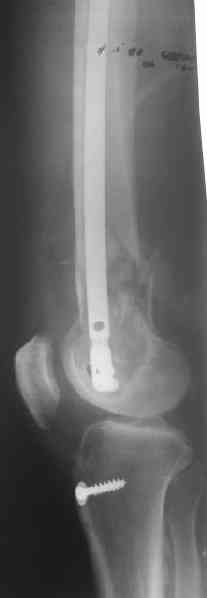

Удалили ластину без проблем. Выявилась значительная подвижность. В этих условиях сразу пропала мотивация к постепенной коррекции аппаратом. Попробовал восстановить длину, введя между отломками spreader. Отчасти удалось. Тогда защили рану, наложили спицевой дистрактор (2 спицы в дистальный отдел и 1 вверху). после этого был убран и спонгиозный винт. И сделали антгерадное штифтование, как говорится, "по принятой в

клинике методике".

Длину восстановили, возможно, даже с изьбытком, ну да динамизируем пораньше. Введенные в овальное отверстие дистальые винты имеют угловую стабильность. Снимки приложены. Заранее спасибо за критику и комментарии.